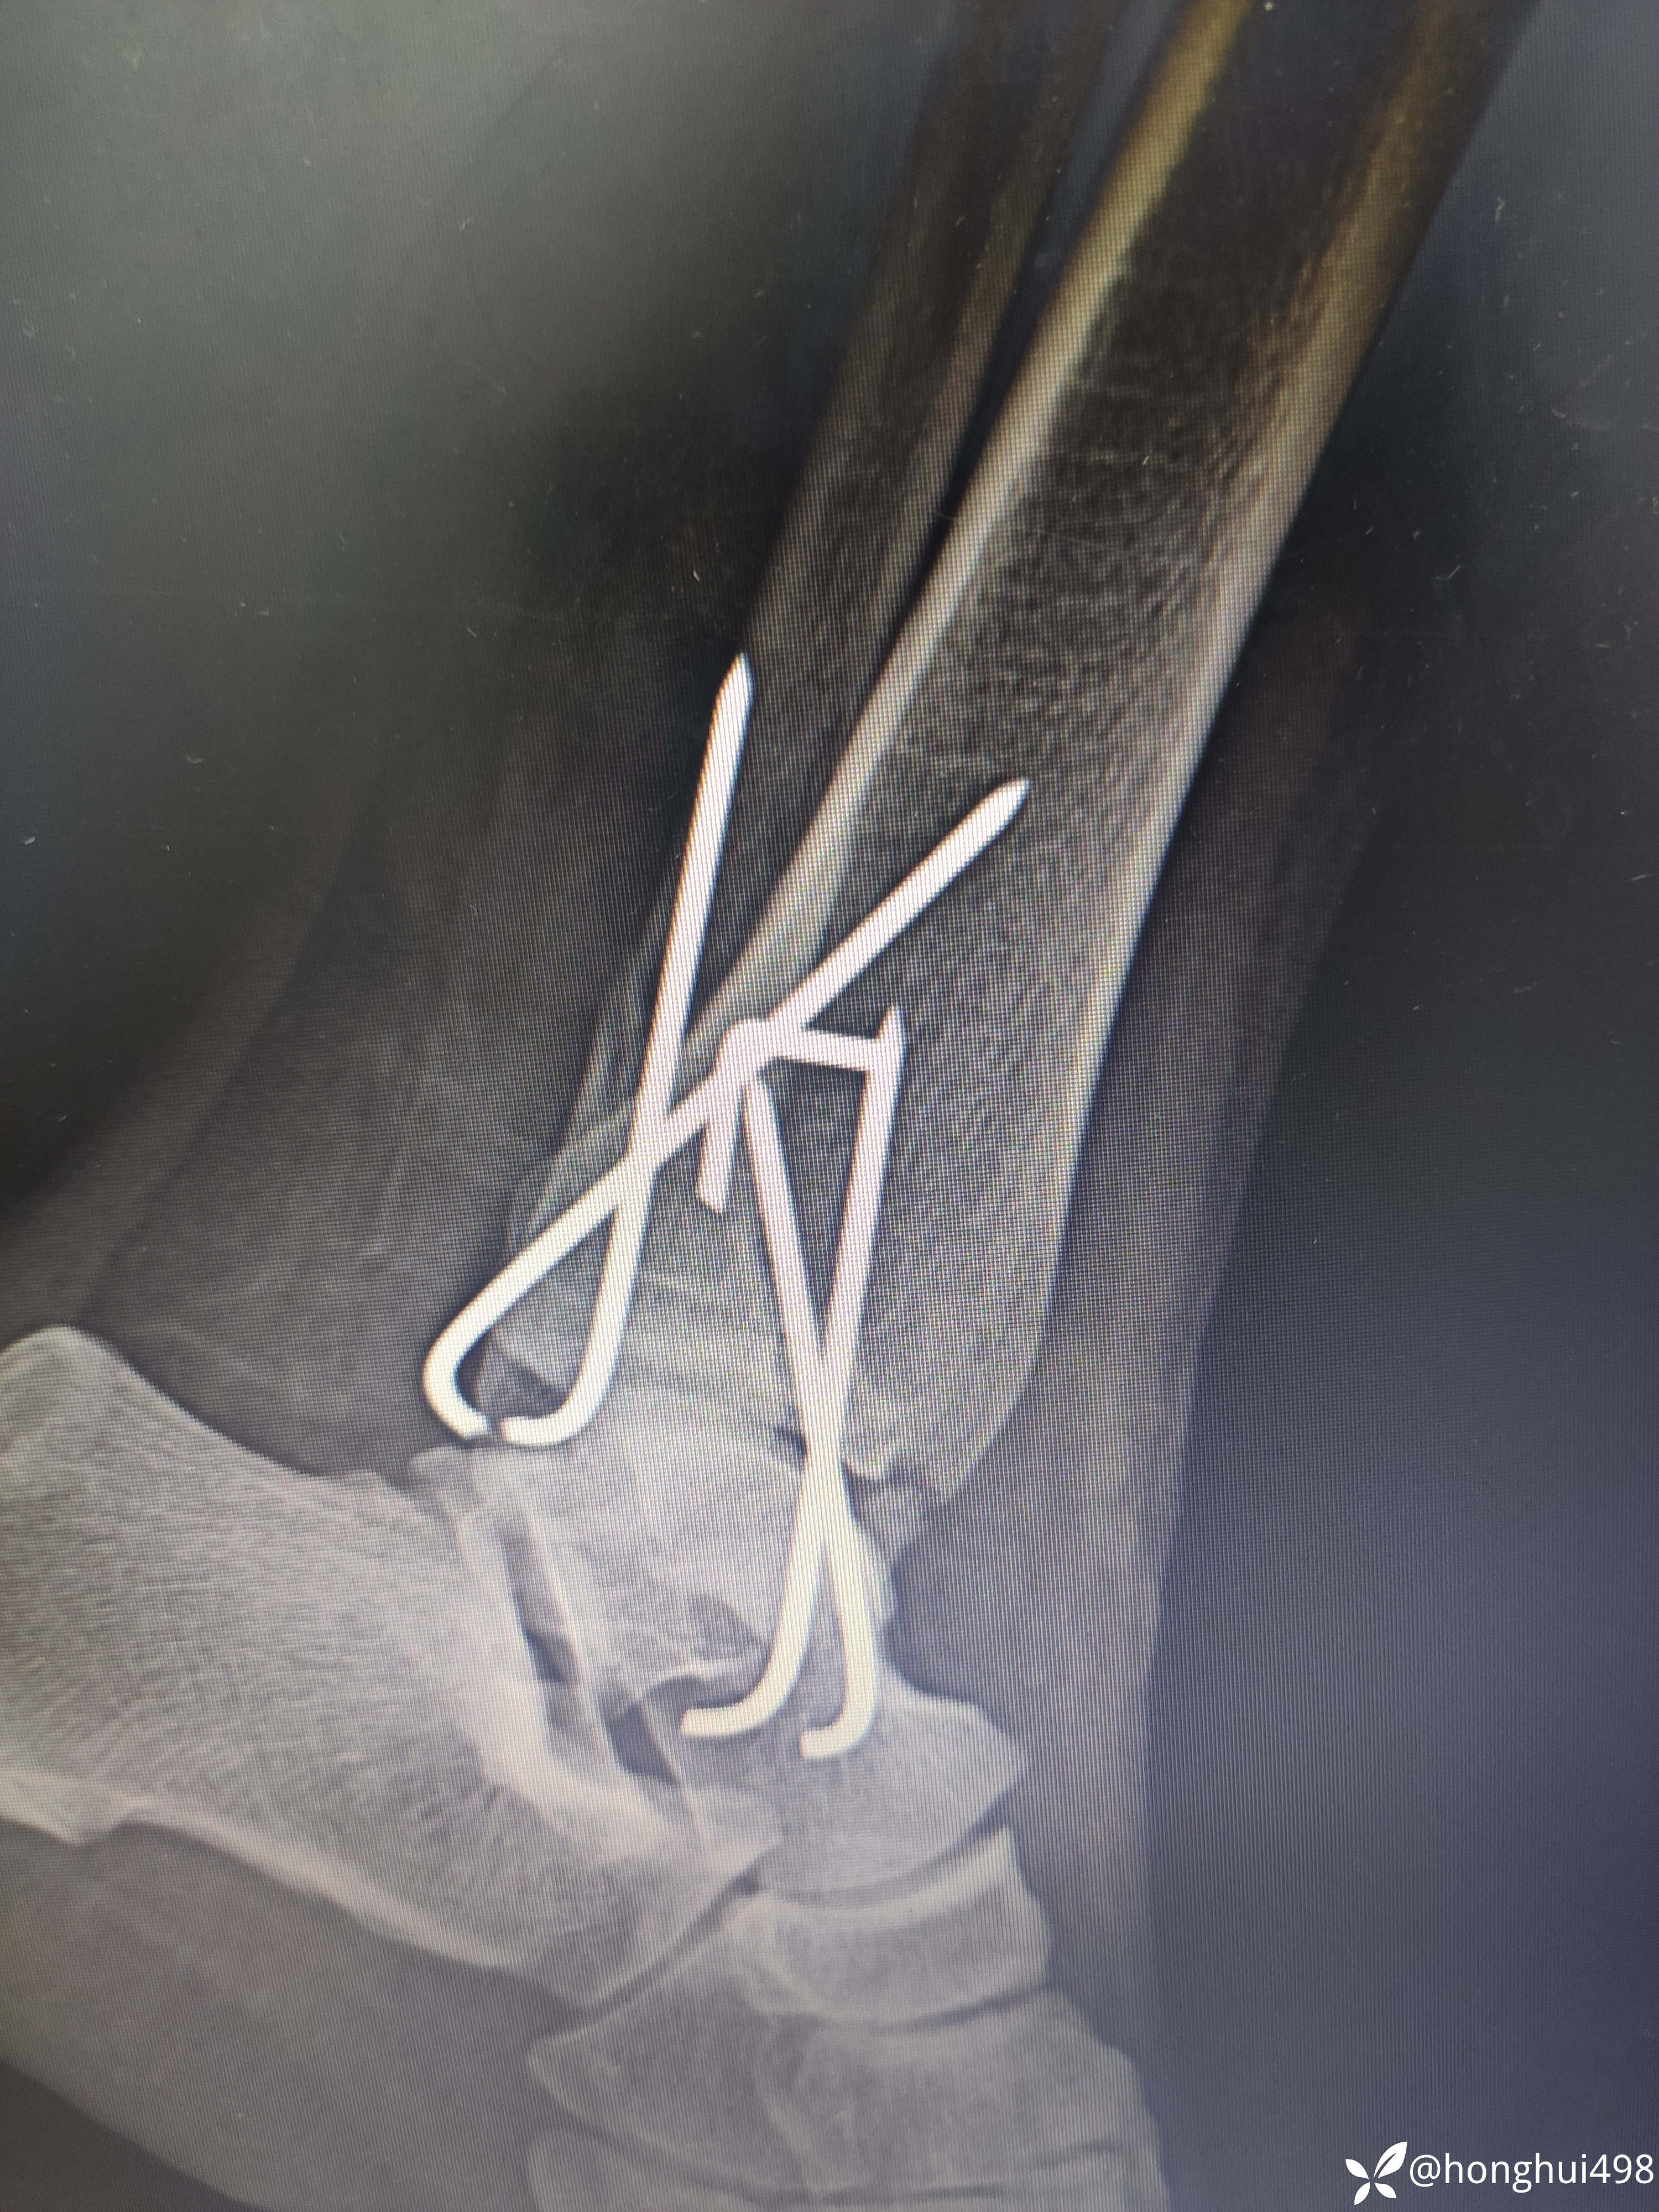

杨庆运骨伤科医生 达人已点赞女性53岁,因摔伤致左踝关节疼痛出血在当地私立医院手术治疗,据患者说内踝又挫裂伤口,诊断左踝关节骨折脱位开放性,予急诊手术克氏针内固定。术后第二天因子女都在城里上班为了方便照顾到我院要求住院治疗。

这看起来做的挺好,可是这下胫腓克氏针我该如何评价,该不该负重,等骨折愈合关节也僵硬了,如何规范治疗?